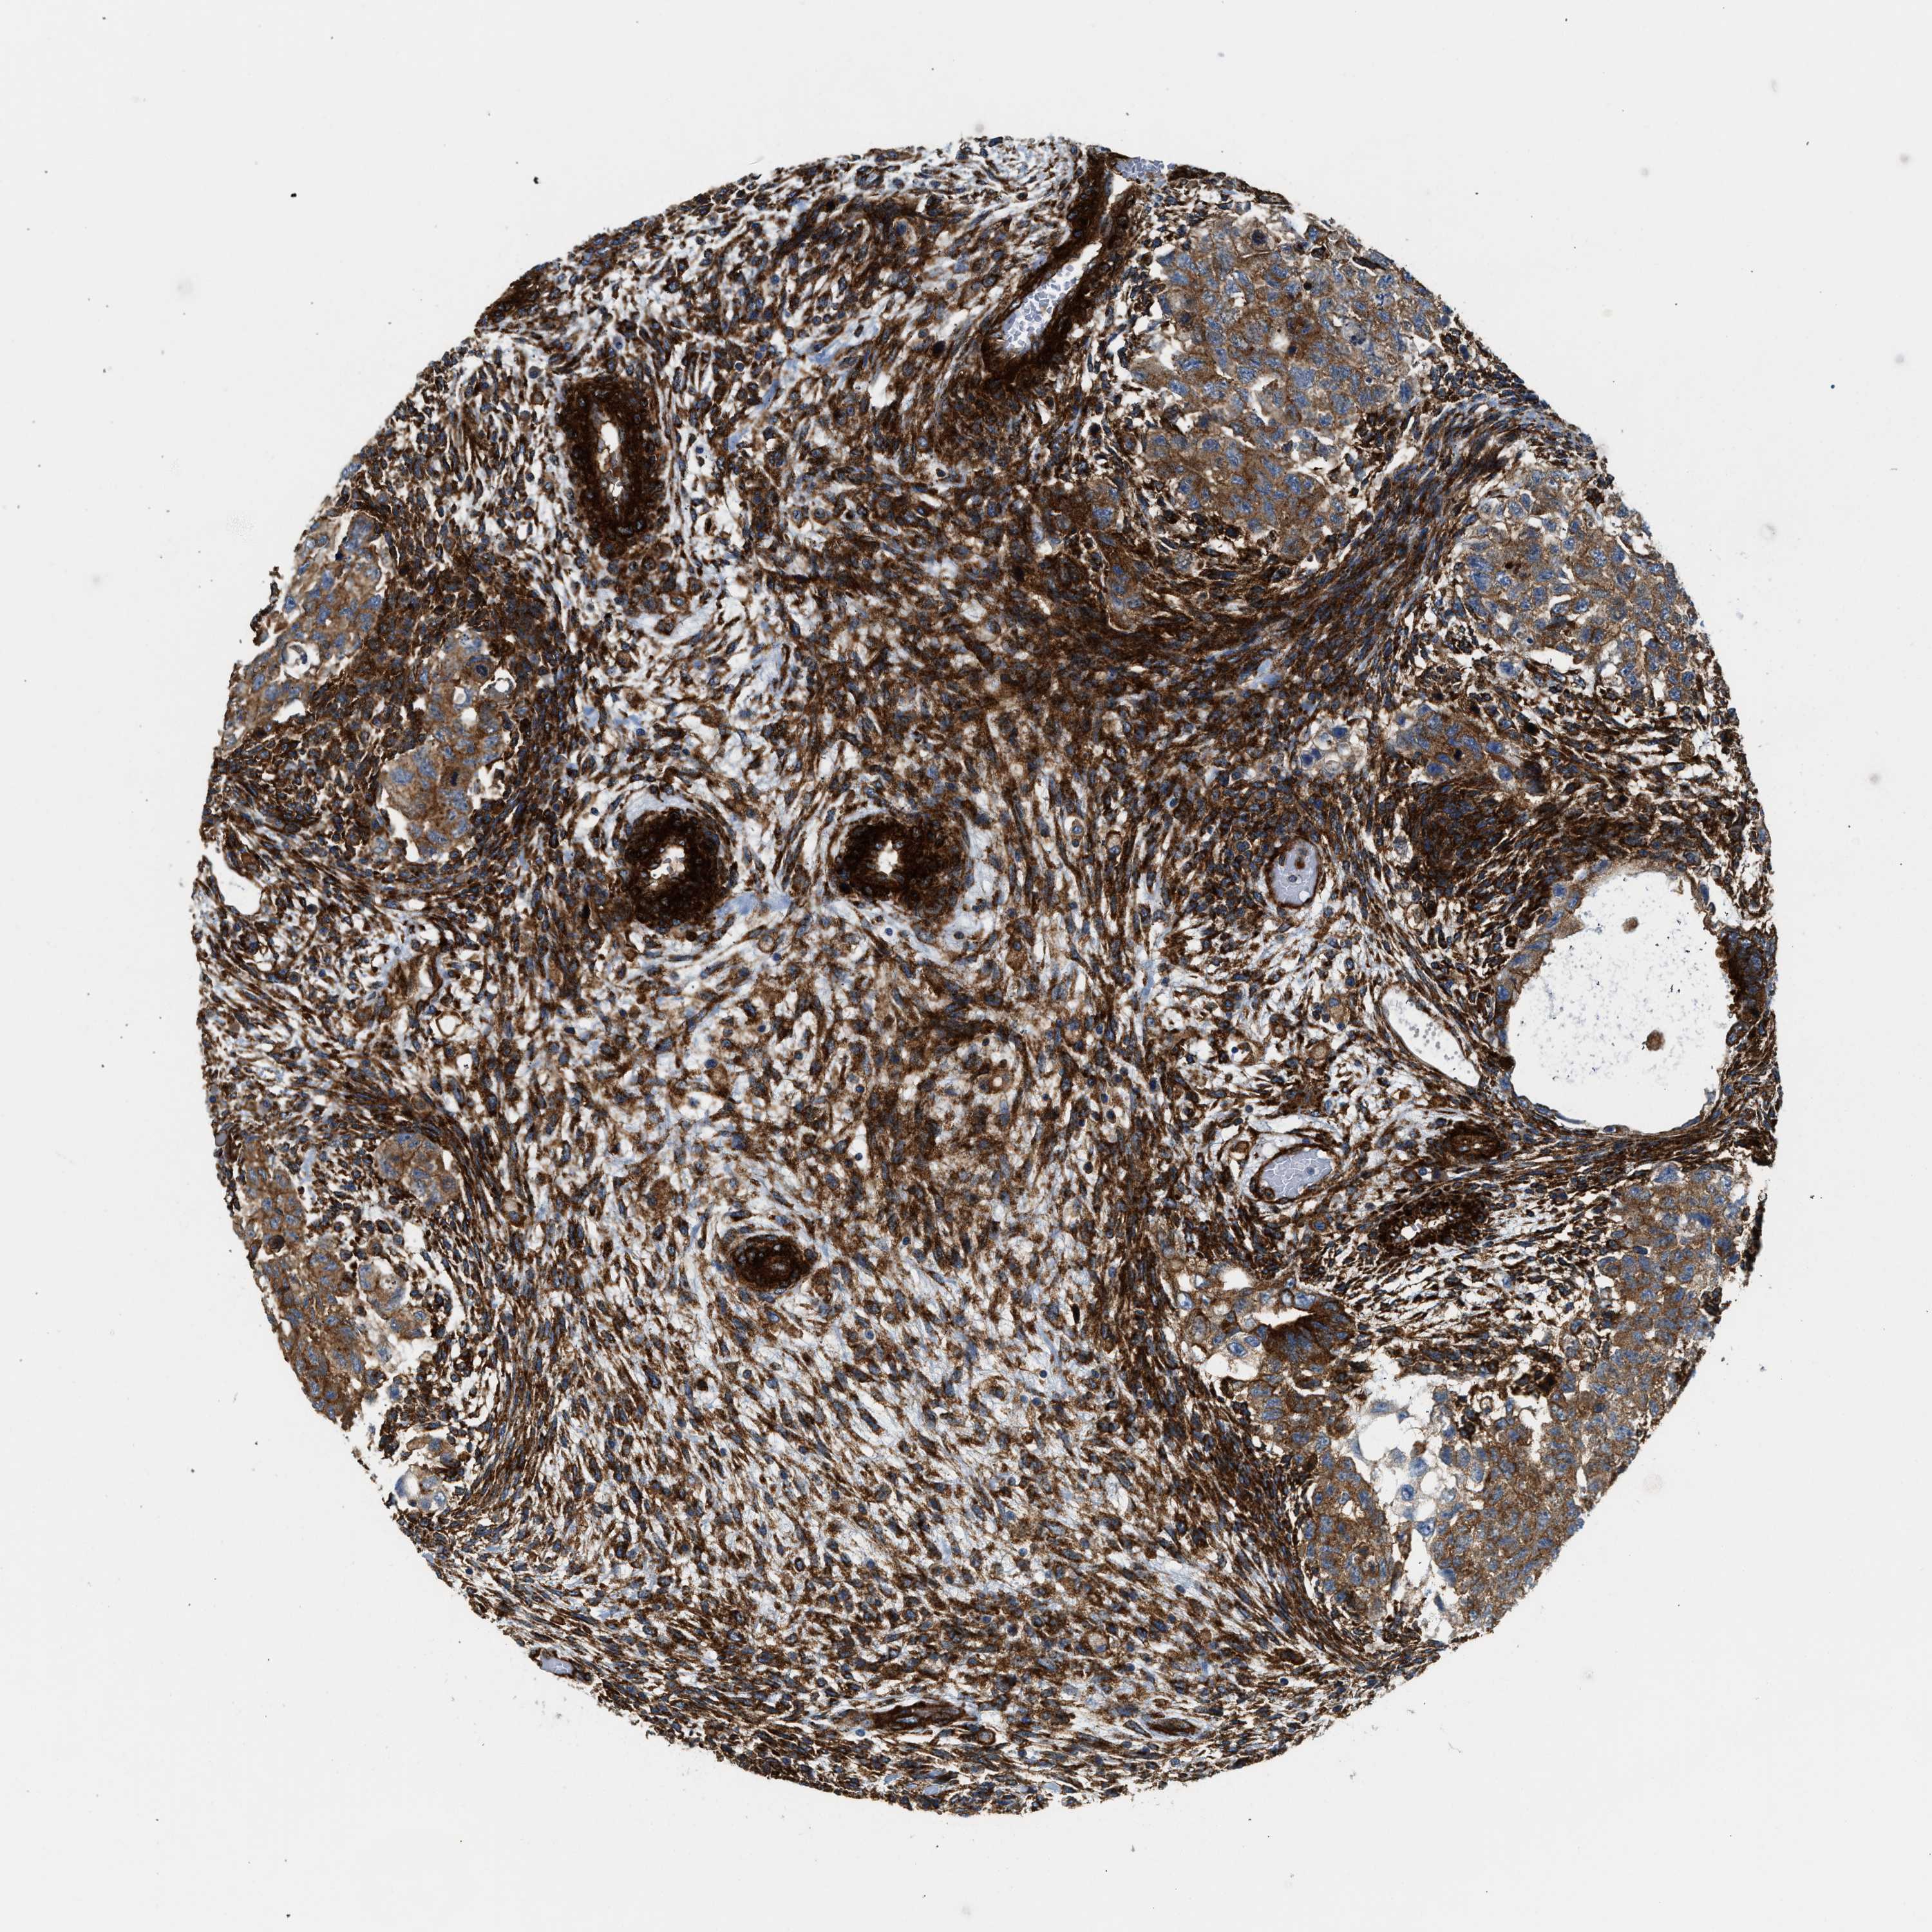

TESTIS CANCER - Protein expressioni

A mouse-over function shows sample information and annotation data. Click on an image to view it in a full screen mode. Samples can be filtered based on level of antibody staining by selecting one or several of the following categories: high, medium, low and not detected. The assay and annotation is described here.

Note that samples used for immunohistochemistry by the Human Protein Atlas do not correspond to samples in the TCGA dataset.

Antibody stainingi

Antibody staining in the annotated cell types in the current human tissue is reported as not detected, low, medium, or high, based on conventional immunohistochemistry profiling in selected tissues. This score is based on the combination of the staining intensity and fraction of stained cells.

Each image is clickable and will lead to virtual microscopy that enables deeper exploration of all samples and also displays staining intensity scores, fraction scores and subcellular localization as well as patient and tissue information for each sample.

Antibody CAB015334

Carcinoma, Embryonal, NOS

Seminoma, NOS